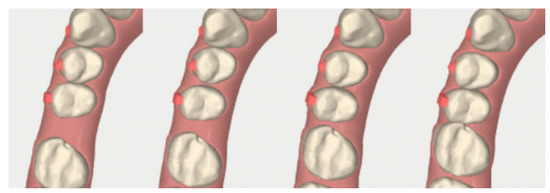

2.3.1. Example—Anterior Open-bite

2.3.2. Example 2—Extraction Space Closure